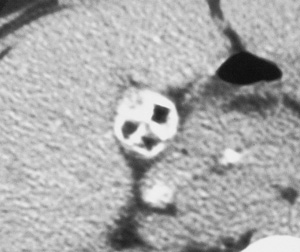

Halloween CT cholangiogram

Med J Aust ; (8): 461. || doi: 10.5694/j.1326-5377.2002.tb04899.x

Published online: 21 October 2002